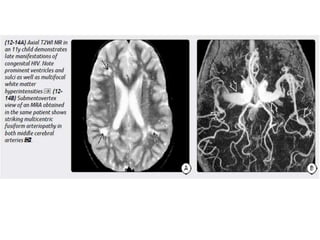

Congenital (Perinatal) HIV

Imaging

Atrophy, particularly in the frontal lobes.

Bilaterally symmetric basal ganglia calcifications.

Ectasia and fusiform enlargement of intracranial arteries.

Strokes with foci of restricted diffusion and subarachnoid hemorrhage

may occur as complications of the underlying vasculopathy.

Congenital (Perinatal) HIV Imaging Atrophy,particularly in the frontal lobes. Bilaterally symmetric basal ganglia calcifications. Ectasia and fusiform enlargement of intracranial arteries. Strokes with foci of restricted diffusion and subarachnoid hemorrhage may occur as complications of the underlying vasculopathy.